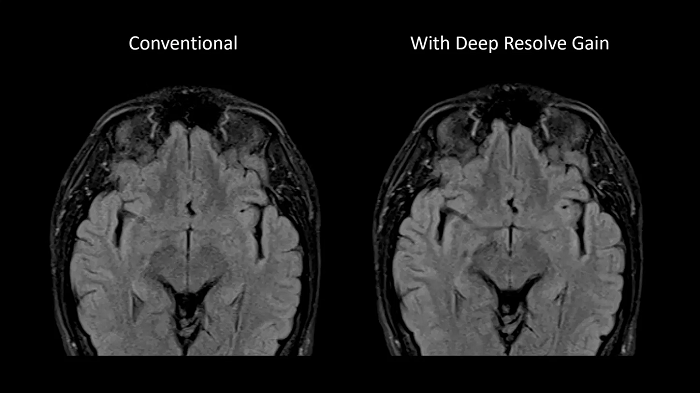

Deep Resolve Gain

Deep Resolve Gain, a constructive technique, utilizes individual quantitative noise maps in the reconstruction process for targeted denoising. It increases image quality to ensure the best diagnostic abilities and is available for a wide range of sequences.

Image Courtesy: University Hospital Erlangen, Germany | Image-ID: 4aaaa0297